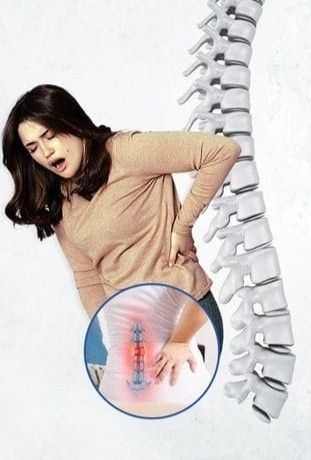

Omurlar arasındaki disklerin yapısal bozuklukları, sinirlere baskı yaparak sık görülen bir sağlık sorununa yol açar. Bu durum, sadece bel ağrısına yol açmakla kalmayıp vücudun farklı bölgelerini ve organlarını da etkileyebilir. Peki bel fıtığı hangi organlara zarar verir? Bu sorunun cevabı, belirtilerin çeşitliliğine ve fıtığın şiddetine bağlıdır. İşte konu ile alakalı merak edilenler!

Bel Fıtığı Hangi Organları Etkiler?

Bel fıtığı, özellikle bel bölgesindeki sinirlere baskı yaptığı için vücudun alt kısmını doğrudan etkiler. Baskı altında kalan sinirler, bacaklarda uyuşma, ağrı ve güçsüzlük gibi şikayetlere neden olabilir. Ancak etkileri bununla sınırlı değildir. Sinir sistemi aracılığıyla idrar yolları, bağırsaklar ve cinsel organlar da dolaylı olarak etkilenebilmektedir.